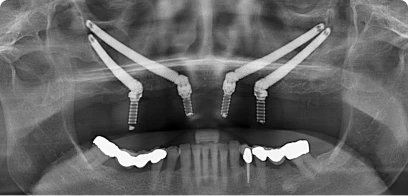

x-ray image of a mouth with 4 zygomatic implants placed in the cheek bone

Zygomatic Dental Implants

These are the longest types of dental implants and can only be placed in the zygomatic bone to hold superstructures. They are the only option when there is an advanced deterioration of the upper jaw bone.